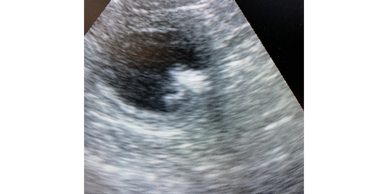

Basic ultrasound, whether to check for pregnancy or to look a little closer at a possible area of concern